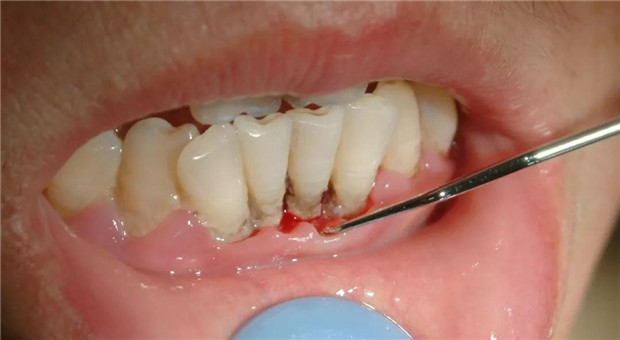

健康每一天,从爱牙开始!在这世界爱牙日来临之际,小编来给大家分享一些有关牙周病的科普知识。

一、牙周疾病概述

牙周疾病特指只发生在牙周支持组织的各种疾病。包括牙龈、牙骨质、牙周韧带和牙槽骨因炎症所致的一种疾病,是最常见的口腔疾病之一,也是导致牙齿丧失的一个主要原因。但患者并非所有这些组织都同时患病,视局部炎症的轻重及范围,实际上牙周病可分为牙龈病和牙周炎二大类。

三、预防牙周疾病—洁牙

洁牙,俗称洗牙,专业术语龈上洁治术,是指用洁治器械去除牙龈上牙石、菌斑和色渍,并磨光牙面,以延迟菌斑和牙石再沉积。牙菌斑和牙结石是牙周病最主要的局部刺激因素,洁治术是去除龈上菌斑和牙石最有效的方法。洗牙的主要目的是为了防治口腔疾病,而不单纯是为了好看。通过洗牙可以减轻牙龈炎、牙周炎的炎症状况。